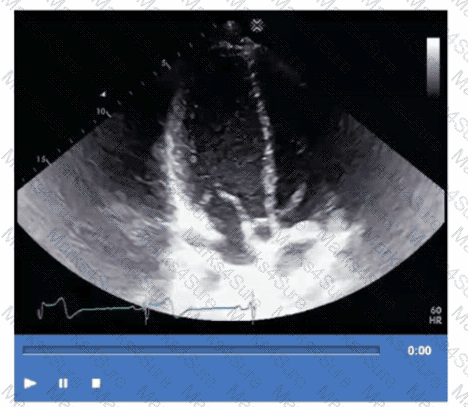

Which is the most likely abnormality represented in these images from a 48-year-old man with shortness of breath?